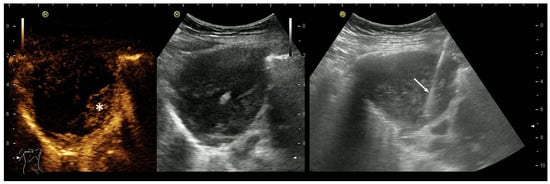

2. Primary Pulmonary Sarcomas

3. Pleural Mesothelioma